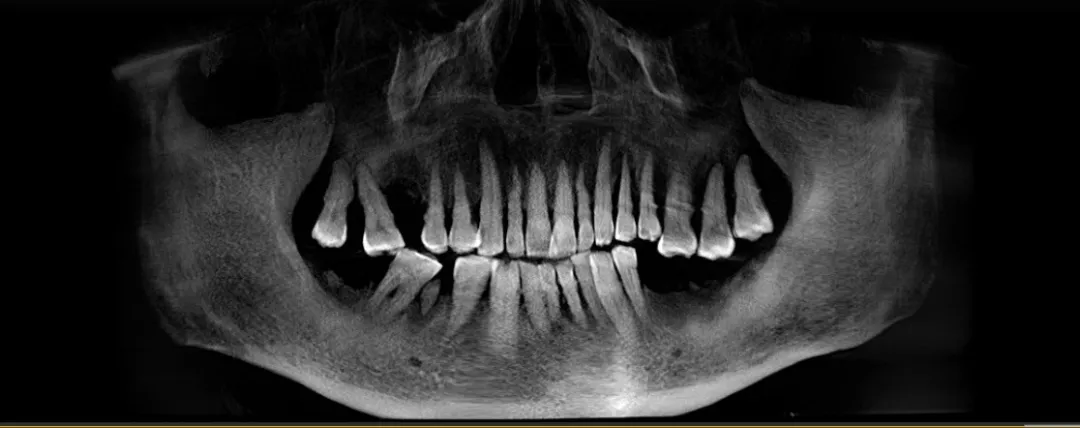

患者术前牙片

长此以往,从20多岁的牙齿断裂,到后来渐渐掉落、松动……这些年里,周爷爷的牙齿陆续脱落,仅剩的牙齿也仿佛“挂”在了他的嘴里,只要稍微用力,这些牙齿随时都能脱落。